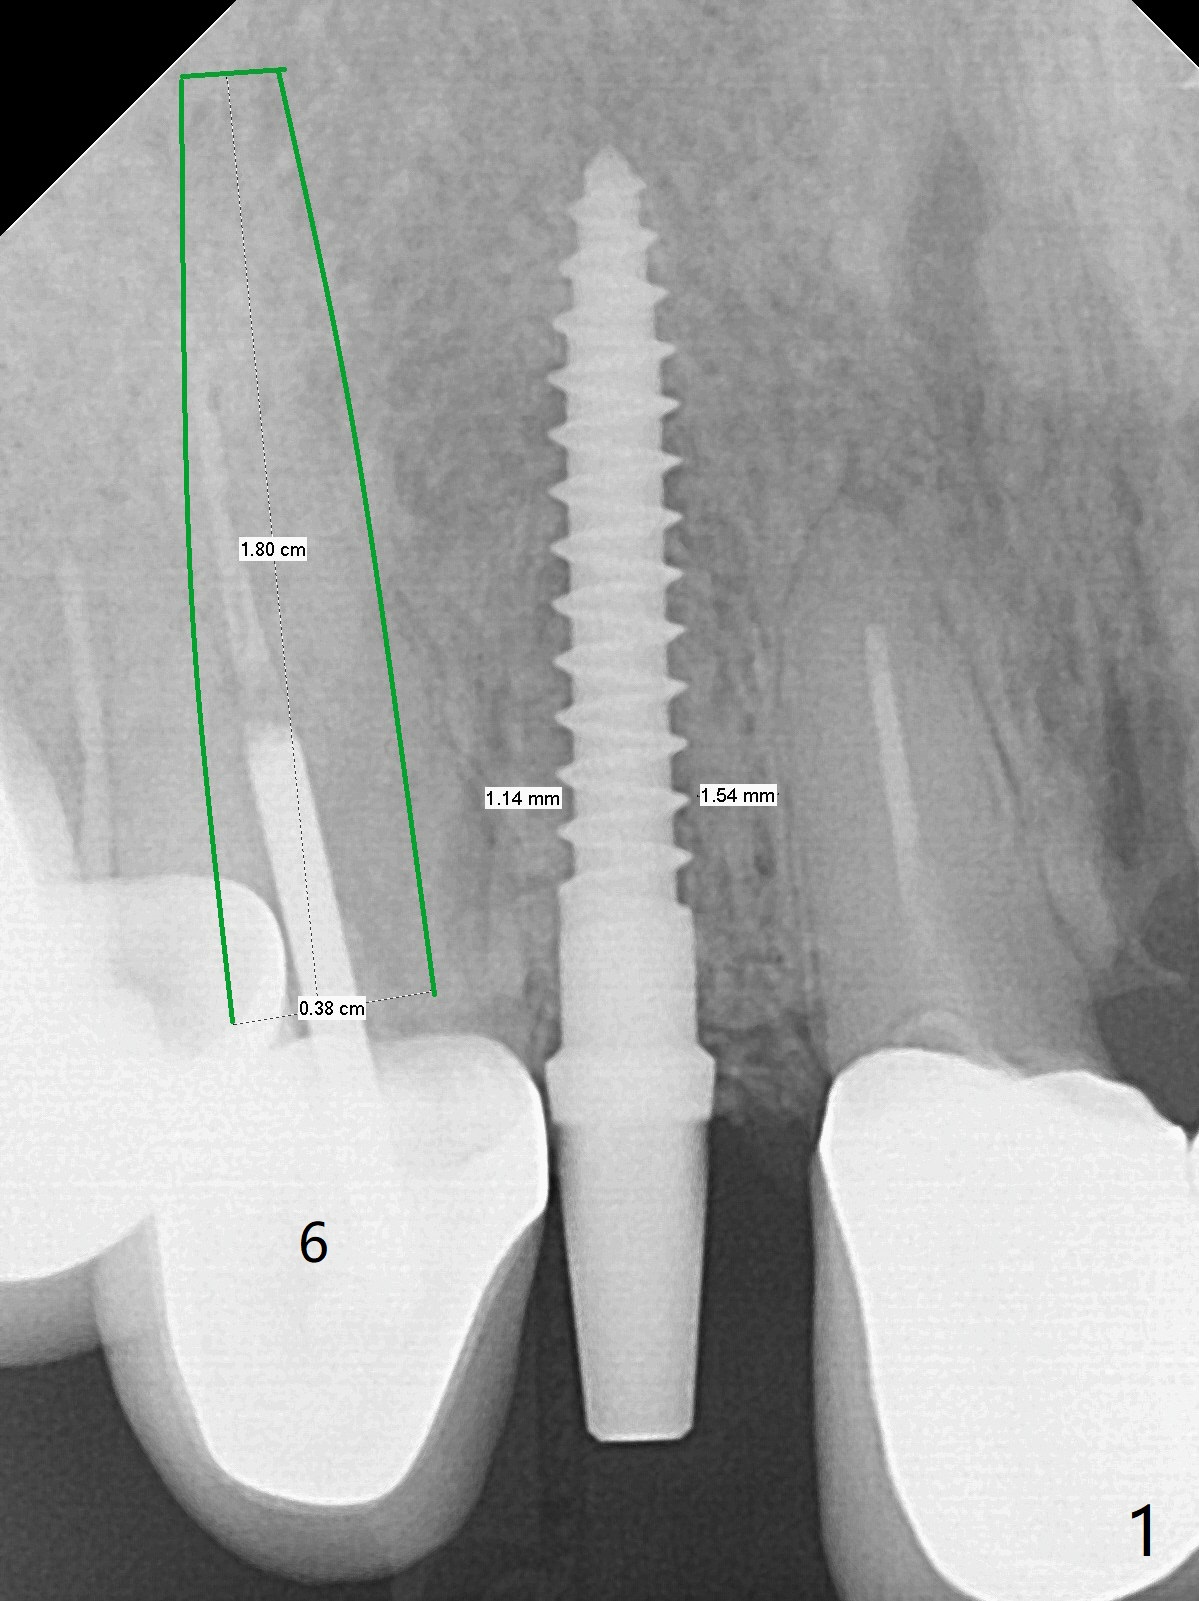

A 90-year-old petit woman fractures the tooth #6 equigingival 5 years 5 months post cementation of #7 crown (Fig.1). Since the palatal crest is high (Fig.2 <), the implant should not be too long (Fig.3, IS Mini-implant). Sticky bone if possible. Undrill considering osteoporosis. Return to Protect Graft No Antibiotic 10 Xin Wei, DDS, PhD, MS 1st edition 07/10/2021, last revision 08/08/2021